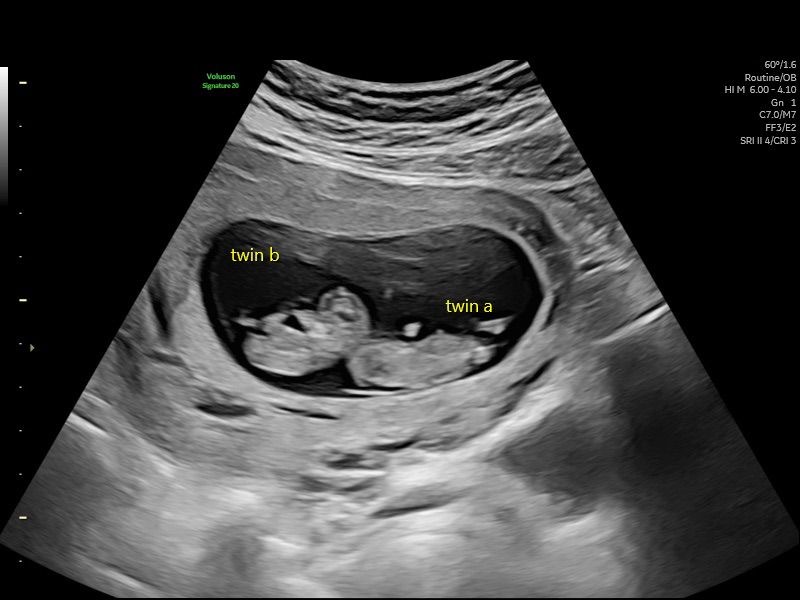

Early Pregnancy Scan (5-12 Weeks)

An early pregnancy scan is often one of the most reassuring steps in early pregnancy. At HerView, we understand that these first weeks can be both exciting and emotional, and many women simply want clarity, comfort, and a first connection with their growing baby. Our Early Pregnancy Scan, carried out…